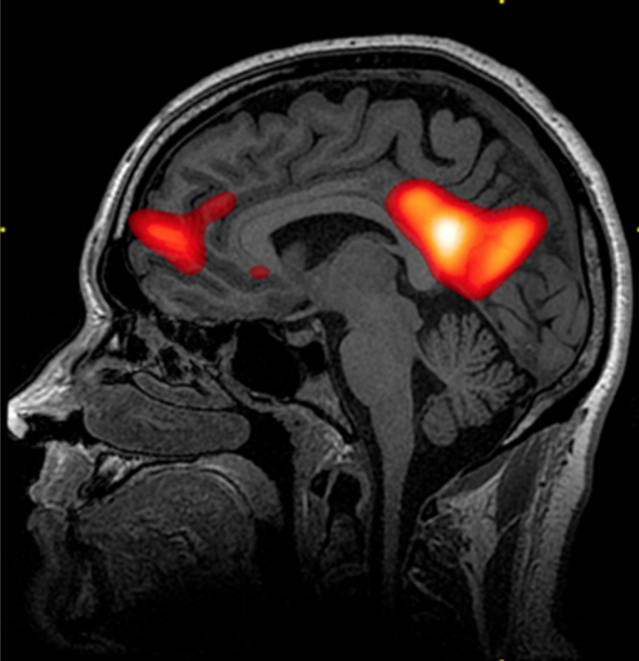

By using MRI scanning technology, researchers were able to investigate the effects of biological factors on behaviour and make a correlation between certain brain areas and memory and other behaviour. The structures would not be able to be clearly seen using other technologies such as EEGs or CTs.

One of the measures used by the researchers was MRI scanning, the results of which told them how active the participant's amygdala had been, and exactly which part of the amygdala had been active during scanning i.e. the researchers relied on sophisticated, precise techniques to know what impact the scenes were having on the participants.

Tierney utilised PET scans to investigate the biological factors in MA and observe the areas of the brain (LOF) linked to language and language acquisition. The ongoing activity in the brain would not be able to be seen using other technologies such as EEGs or MRIs. Introduce StudyConnection of study to question: